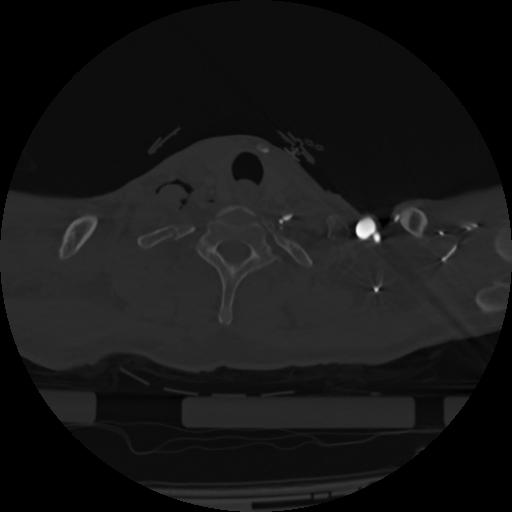

22 ANGIO,CE,Vol,0.5,ANGIO,,